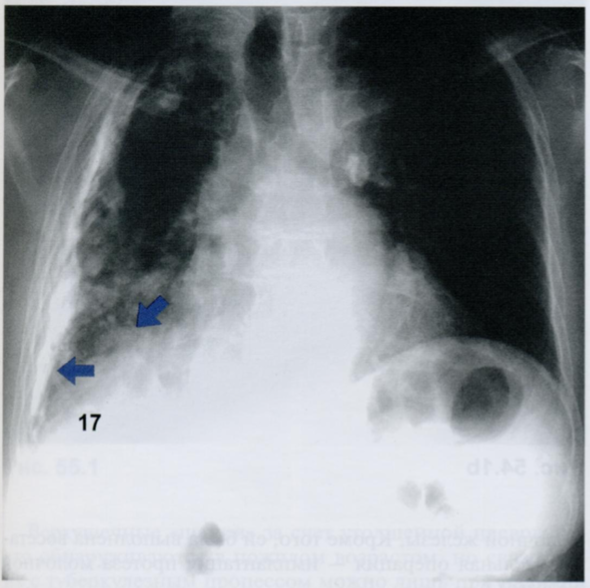

Q

Оцените снимок.

Что из себя представляют плевральные бляшки?

A

Плевральные бляшки представляют собой очаговые утолщения париетальной плевры. Они состоят из скопления гиалинизированных коллагеновых волокон, почти всегда образующихся в результате асбестозной пролиферации.

Они часто развиваются в латеральных отделах грудной стенки и в базальном отделе около диафрагмы. В отличие от остаточных изменений после воспалительного процесса, асбостозные изменения («асбестоз плевры») часто приводят к двусторонному утолщению париетальной плевры.

У пациента на снимке определяются двусторонние диафрагмальные плевральные бляшки и дополнительные бляшки рядом с перикардом (стрелки).